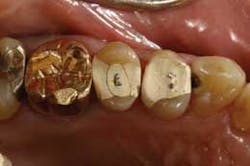

From the very first three units I cemented, I knew there was something special about the Wol-Ceram system. These were the first all-ceramic crowns I had ever inserted that felt like PFMs as they slid down into place. There is nothing quite so reassuring as being able to feel the mechanical retention of a crown as it moves down the prep.